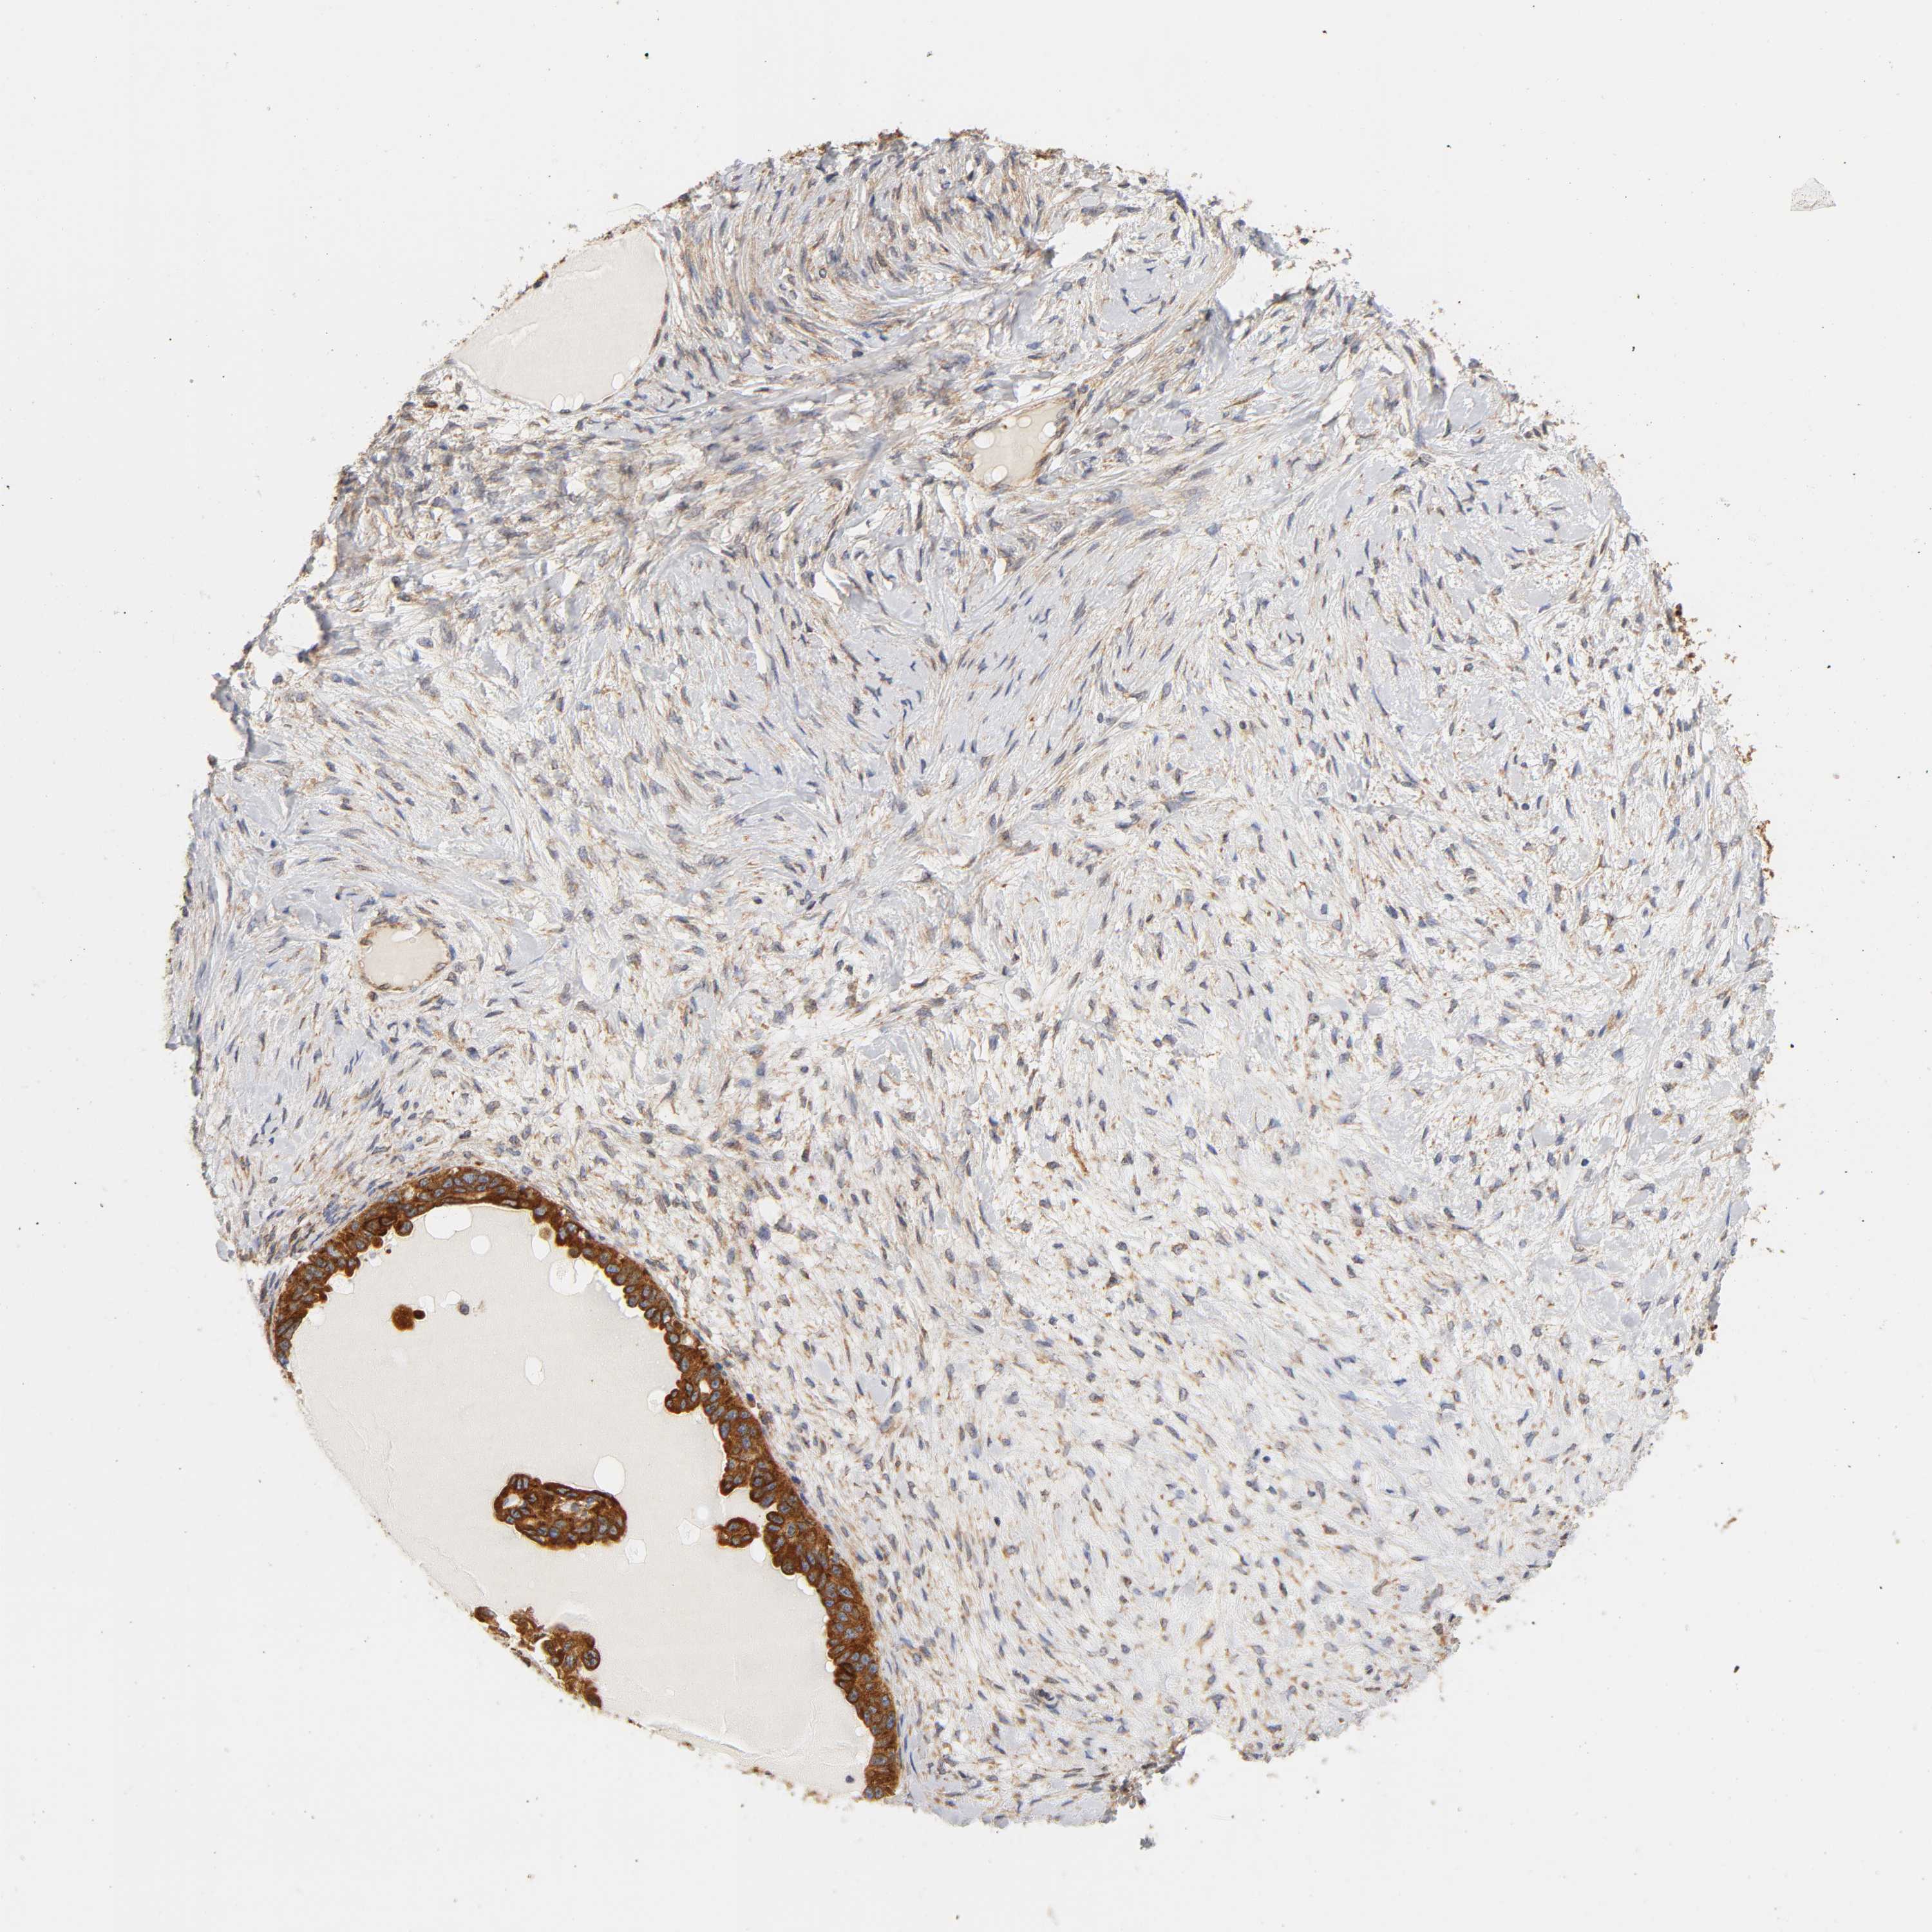

OVARIAN CANCER - Protein expressioni

A mouse-over function shows sample information and annotation data. Click on an image to view it in a full screen mode. Samples can be filtered based on level of antibody staining by selecting one or several of the following categories: high, medium, low and not detected. The assay and annotation is described here.

Note that samples used for immunohistochemistry by the Human Protein Atlas do not correspond to samples in the TCGA dataset.

Antibody stainingi

Antibody staining in the annotated cell types in the current human tissue is reported as not detected, low, medium, or high, based on conventional immunohistochemistry profiling in selected tissues. This score is based on the combination of the staining intensity and fraction of stained cells.

Each image is clickable and will lead to virtual microscopy that enables deeper exploration of all samples and also displays staining intensity scores, fraction scores and subcellular localization as well as patient and tissue information for each sample.

Antibody HPA010136

Antibody CAB004372

Staining

High

Medium

Low

Not detected

Intensity

Strong

Moderate

Weak

Negative

Quantity

>75%

75%-25%

<25%

None

Location

Nuclear

Cytoplasmic/membranous

Cytoplasmic/membranous,nuclear

Cystadenocarcinoma, serous, NOS

Carcinoma, endometroid

Cystadenocarcinoma, mucinous, NOS

Carcinoma, NOS